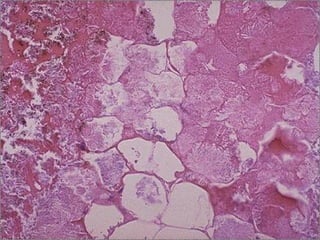

3 stages of coagulative

necrosis (L to R) -- micro

Coagulative Necrosis • Cell’sbasic outline is preserved • Homogeneous, glassy eosinophilic appearance due to loss of cytoplasmic RNA (basophilic) and glycogen (granular) • Nucleus may show pyknosis, karyolysis or karyorrhexis

3 stages ofcoagulative necrosis (L to R) -- micro